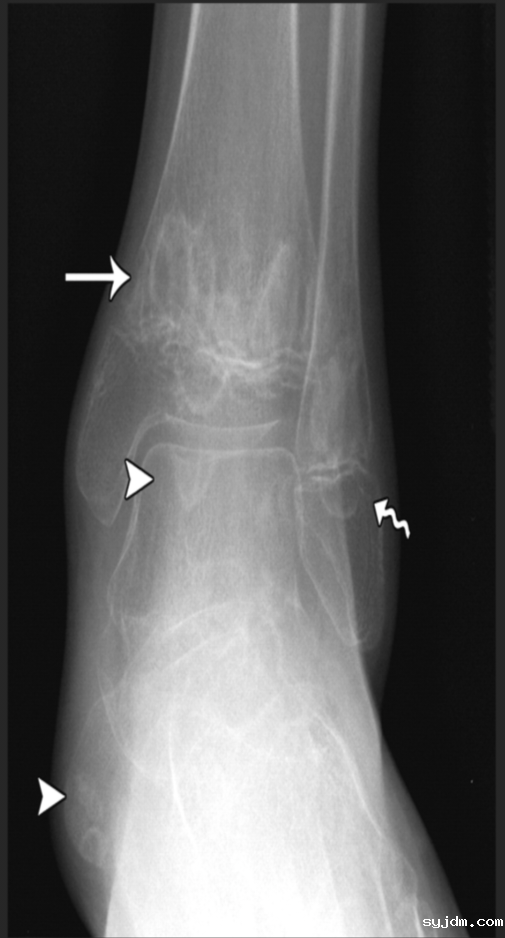

左足正侧位(站立),双手正位放射

1.右手第3远节指骨及左手第5指骨部分缺如:请结合临床病史。2.右侧第2近端指间关节间隙变窄、双侧部分近端指间关节稍肿胀:原因待查,类风湿性关节炎?建议结合临床及相关实验室检查。

图D 踝部多发溶骨改变

X线:早期可正常,后期可见溶骨性破坏、骨质硬化或骨膜反应。

MRI(金标准):T2加权像高信号(骨髓水肿),增强后强化,可发现早期无症状病灶。